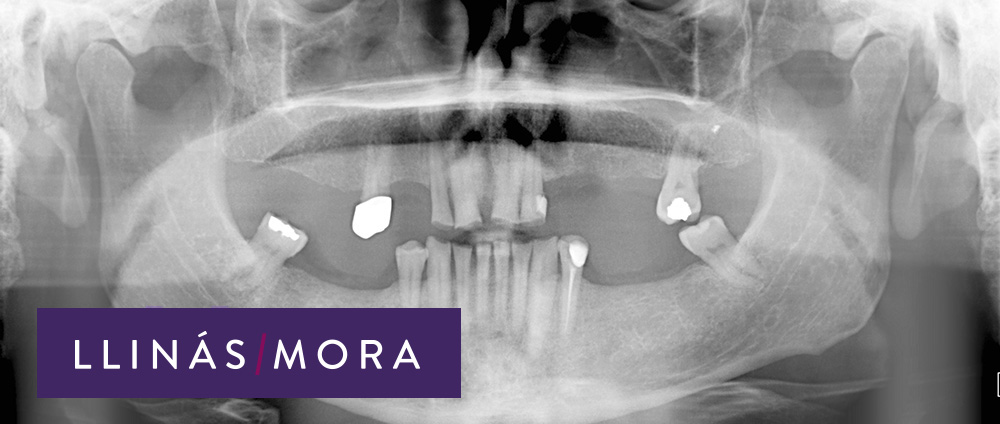

1. Ausencias dentales multiples y mordida descompensada con desgaste avanzado de los dientes.

2. Ausencias dentales multiples y mordida descompensada con desgaste avanzado de los dientes. (Radiografía)